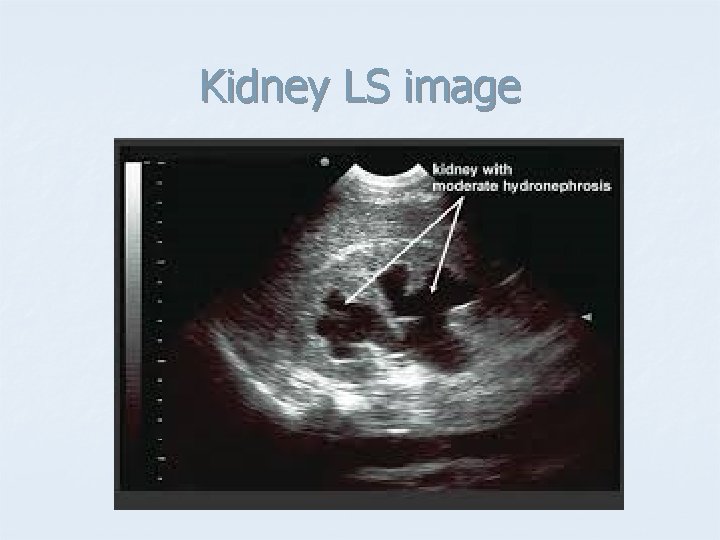

Kidney LS image